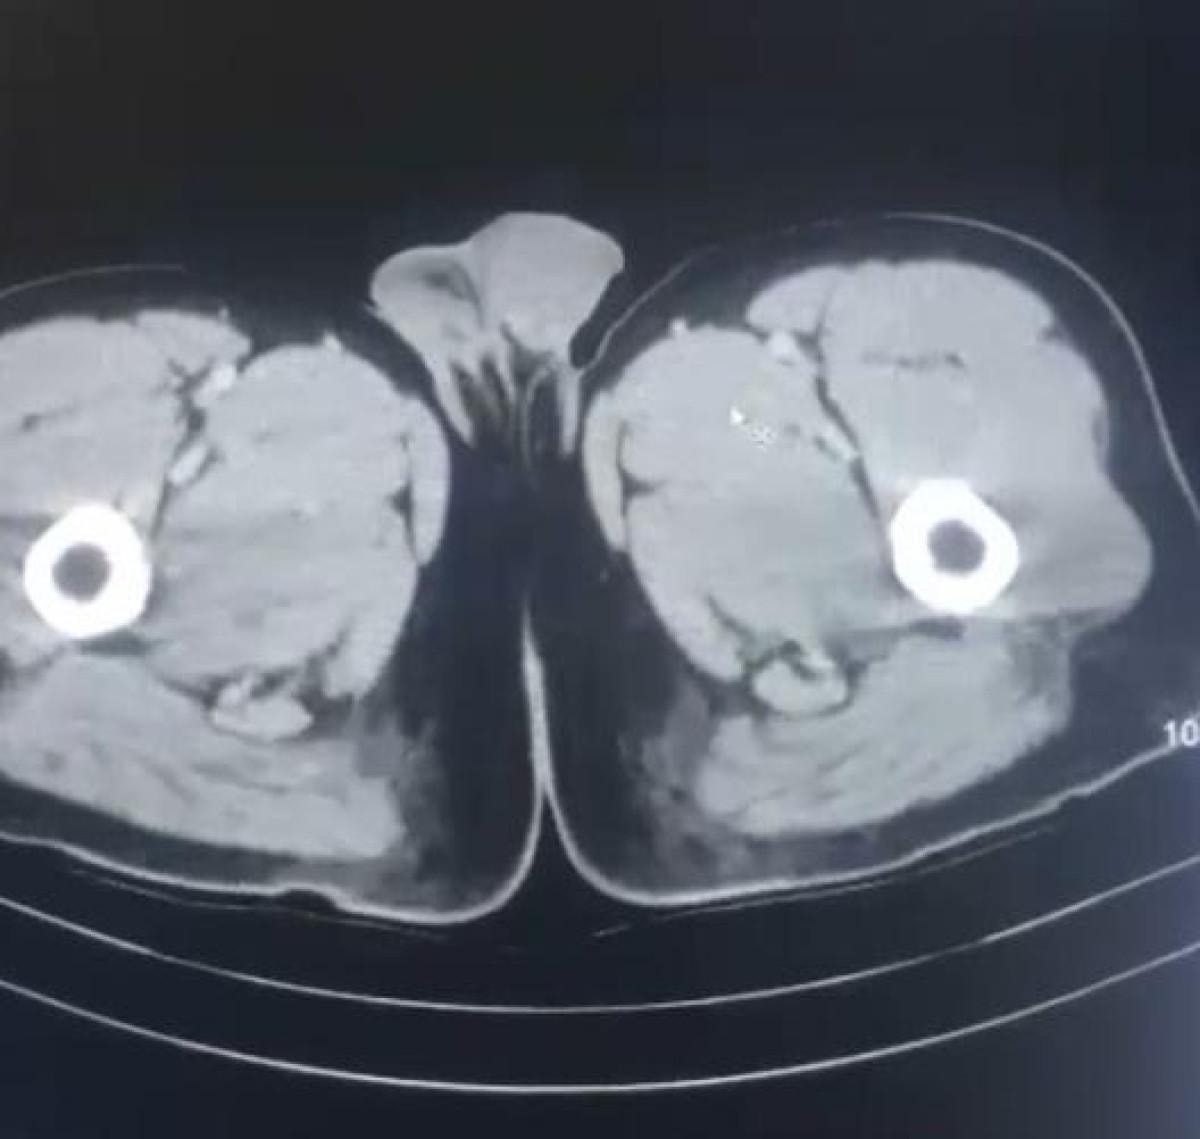

Röntgen ve ultrason sonrası kontrollerde, 3 şüphelinin midesinde uyuşturucu madde olduğu belirlendi.

17 KAPSÜL UYUŞTURUCU YUTTULAR

Şüphelilerin yaklaşık 17 kapsül halinde 212,8 gram uyuşturucu yuttuğu tespit edildi.